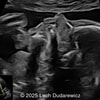

A 33-year-old nullipara with non-contributory medical history presented at 20 weeks, 6 days based on an early scan. Ultrasound revealed the following findings. There were no other apparent abnormalities. What is the most probable diagnosis?